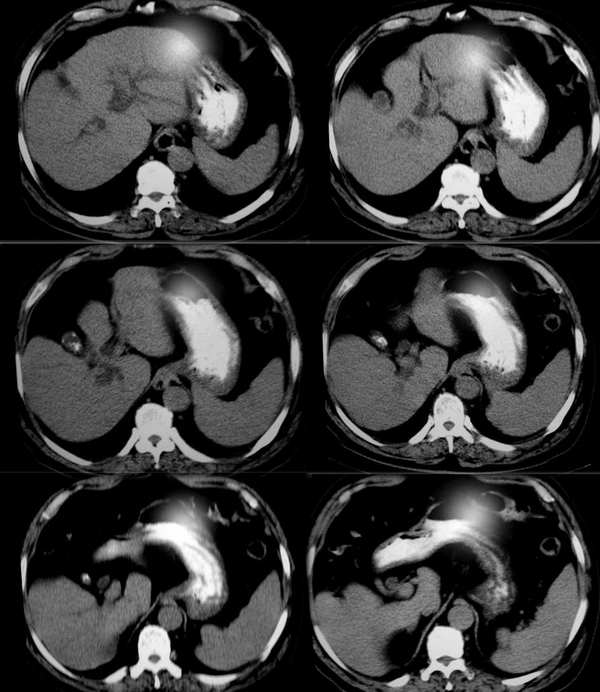

标题: CT2418:求诊:无痛性黄疸10天,无发热。

男,70y,就是单纯无痛性黄疸

肝脏体积不大,肝裂稍宽,肝实质密度均匀,肝内胆管呈枯枝状扩张,在肝门区突然中断,胆总管未见明显增宽,胆囊缩小,壁厚并见斑点状钙化。考虑:1)肝外远侧段肝总管癌,2)慢性胆囊炎。(若能提供年龄、增强片子更好)

肝脏形态不规则,肝裂较宽,尾叶增大;胆囊较小,壁厚,其内可见不规则高密度影;于肝门区见胆总管扩张;胰腺形态密度无著变,羽毛征存在,腹腔内未见明显肿大淋巴结。余(—)

印诊:1、低位胆道梗阻,胆总管扩张,肝内胆管扩张,不除外炎症所致,建议治疗后复查,排除胆总管占位(有条件可以做ercp或ct增强);2、肝硬化;3、胆囊炎,胆囊结石。

肝体积不大,肝裂宽,肝密度均匀,肝内胆管扩张,胆总管突然截断,管壁不规则,管腔呈梅花状,考虑 1)胆总管癌 2)胆囊结石,胆囊炎.